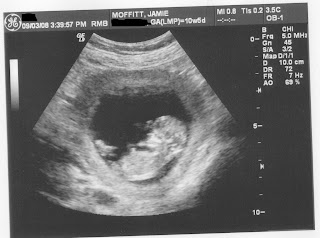

Jamie had an ultrasound the other day. Even though the baby was only 11 weeks old at the time, the technician said she thinks he's a boy, but she can't be 100% certain. I guess we can still be surprised.

Jamie thinks he already looks like a Moffitt. Honestly, I can't tell.